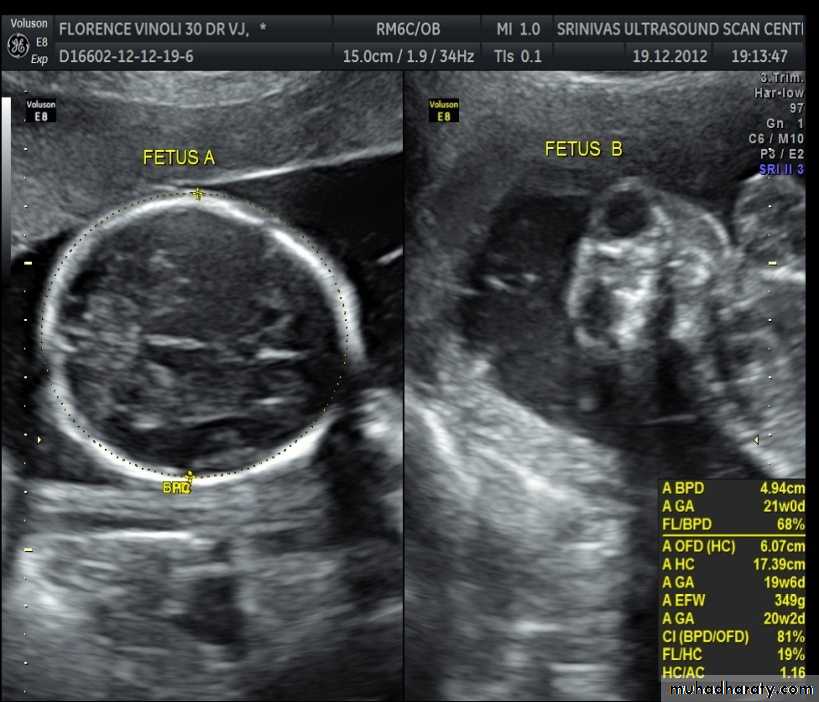

US of the obstetric & Gyne.BPD together with head circumference (HC), abdominal circumference (AC), and femur length (FL) are computed to produce an estimate of fetal weight. In the second trimester this may be extrapolated to an estimate of gestational age and an estimated due date (EDD) .

The BPD should be measured on an axial plane that traverses the thalami, and cavum septum pellucidum. The transducer must be perpendicular to the central axis of the head, and thus the hemispheres and calvaria should appear symmetric.